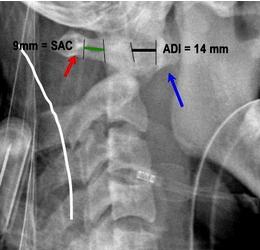

19. Figure A shows the coronal and axial CT images of a 27-year-old male that suffered a fall from a significant height. Which of the following radiographic measurements would best indicate disruption of the transverse ligament.

FIGURES: A

PREFERRED RESPONSE ▼ 4

DISCUSSION: The clinical presentation is consistent with a Jefferson fracture, which is characterized by a fracture of the anterior and posterior arch of the atlas (see illustration A). Treatment of this condition is determined by the stability of the transverse ligament. An intact transverse ligament represents a stable injury which can be treated with a cervical orthosis. A ruptured transverse ligament represents an unstable fracture pattern that should be treated with a halo immobilization or a C1-C2 posterior cervical fusion. Two radiographic parameters that indicate a ruptured transverse ligament are 1) a sum of lateral mass displacement over articular surface of C2 is 8.1mm or greater, and 2) an atlantodental interval (ADI) of 6mm or greater. The historic anatomic study by Spence et al showed that lateral mass separation of > 6.9 mm implied rupture of the transverse ligament. The reference by Heller et al argues that Spence's study did not take into account radiographic magnification, and that transverse ligament rupture should not be inferred unless lateral mass separation is > 8.1 mm. The final reference by Haus et al was a case report of a single patient with a lateral mass displacement of 14mm that was treated successfully with a cervical orthosis only. This is a case report with no statistical significance and should not be referenced to guide treatment. The posterior atlanto-dens interval (PADI) is typically used to evaluate atlantoaxial subluxation. C2 pars